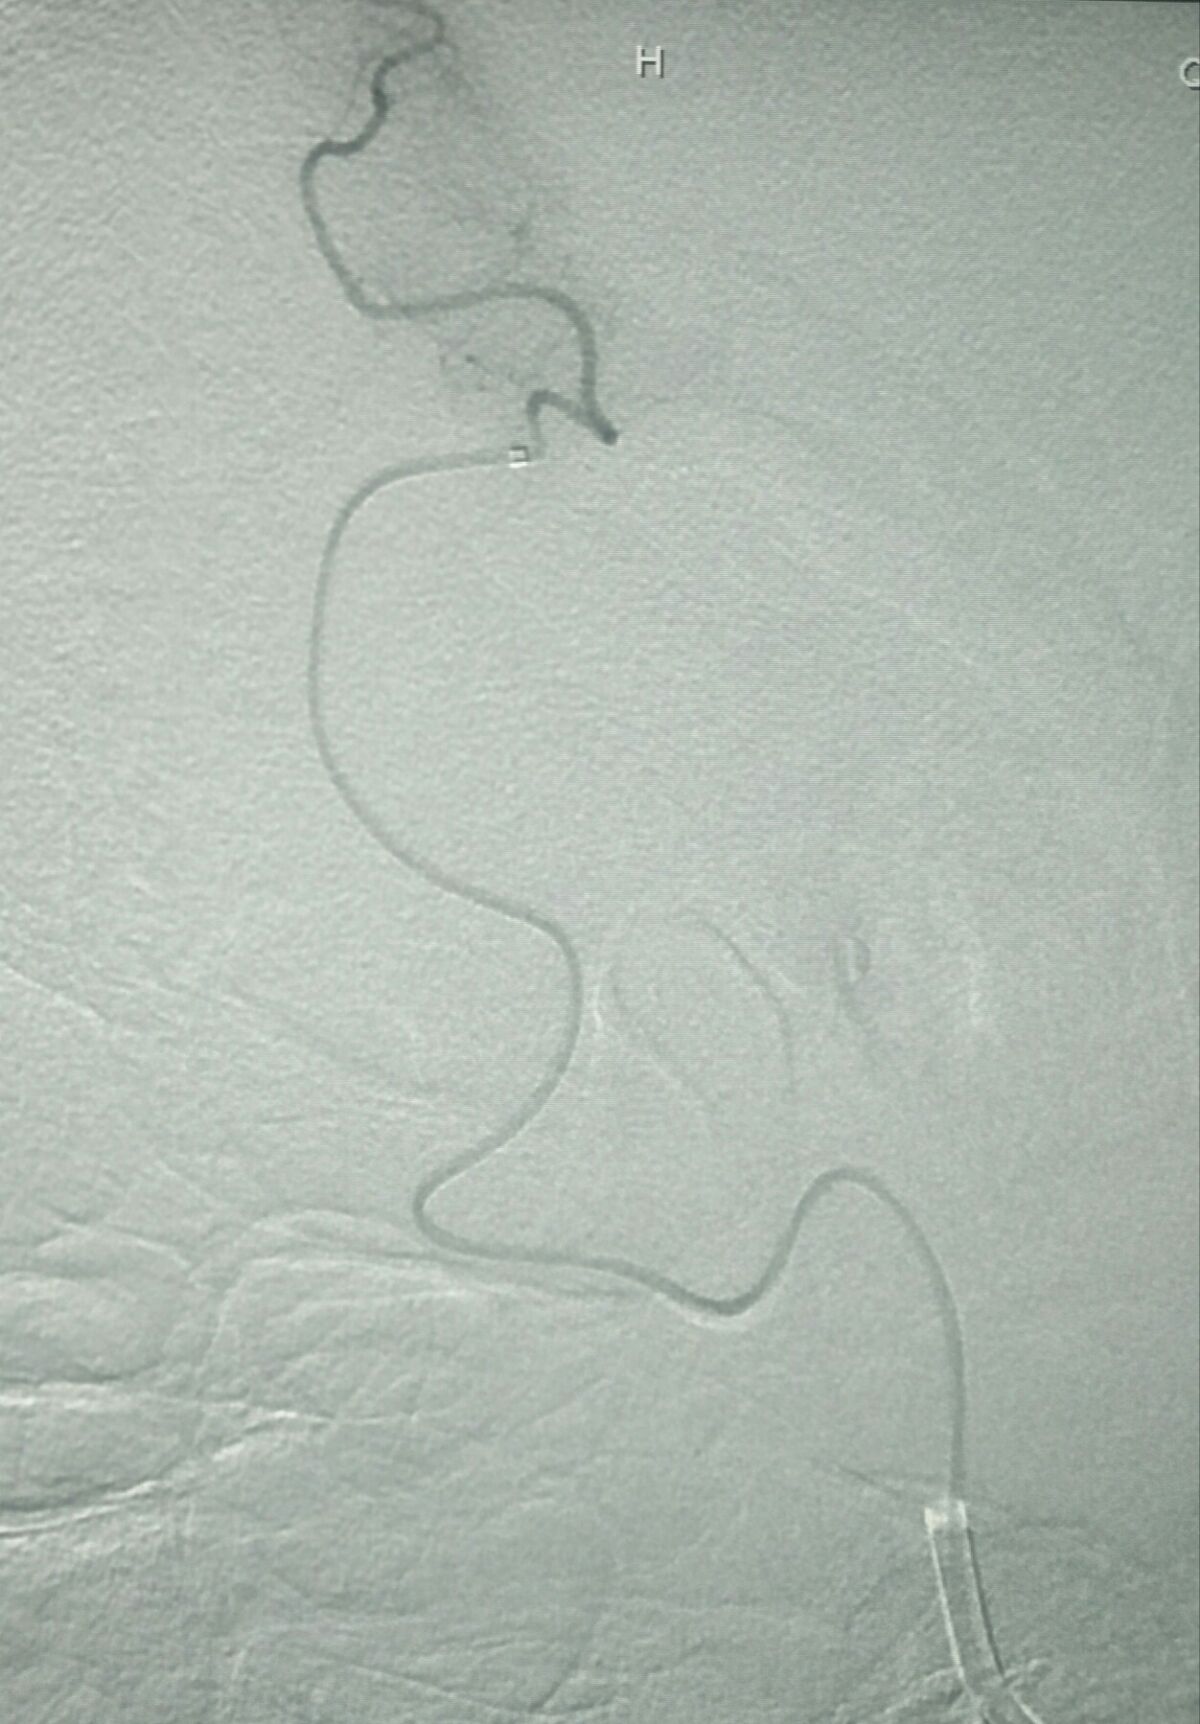

微导管到位M3段并确认真腔